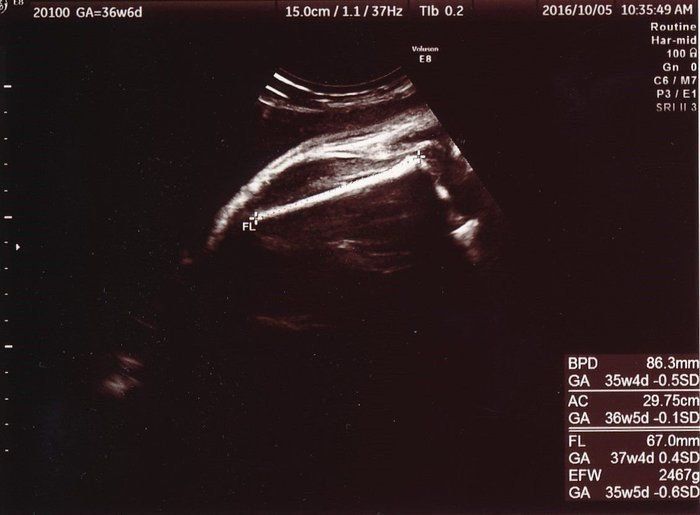

妊娠後期、赤ちゃんが育っていない? エコー写真で振り返る3人目の出産体験 -